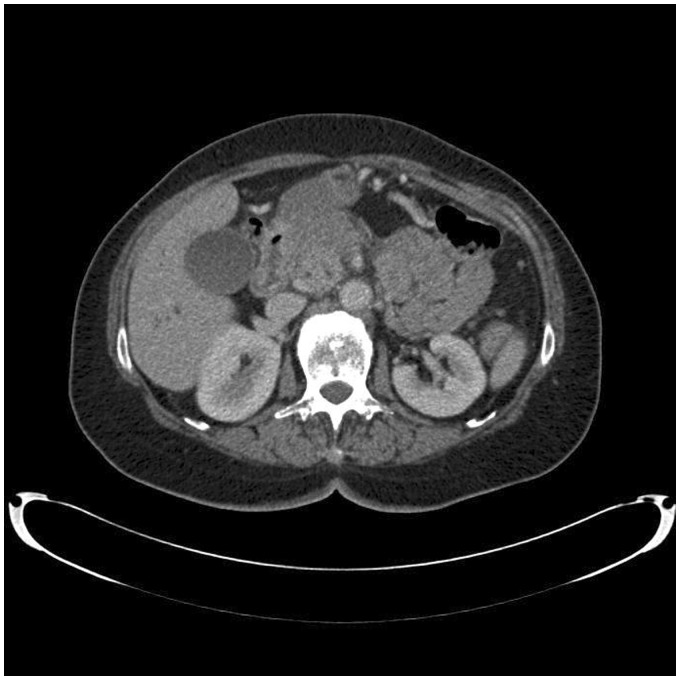

不可逆电穿孔(IRE)是一种消融技术,正在被研究作为胰腺癌的潜在治疗方法。然而,许多患者在胆管内放置金属支架,这被认为是IRE消融术的禁忌症。我们报告一个病例,在胰腺头部区域IRE消融术对患者进行金属支架导致严重的并发症。治疗后,患者出现了多种并发症,包括十二指肠穿孔和横结肠穿孔,以及肠系膜上动脉分支出血,最终导致患者死亡。因此,我们认为如果考虑在金属支架附近进行IRE消融,了解这一点是很重要的。

Irreversible electroporation (IRE) is an ablation technique that is being investigated as a potential treatment of pancreatic cancer. However, many of these patients have a metallic stent in the bile duct, which is recognized as a contraindication for IRE ablation. We report a case in which an IRE ablation in the region of the pancreatic head was performed on a patient with a metallic stent which led to severe complications. After the treatment, the patient suffered from several complications including perforation of the duodenum and transverse colon, and bleeding from a branch of the superior mesenteric artery which eventually lead to her death. Therefore, we believe it is important to be aware of this if an IRE ablation close to a metallic stent is considered.